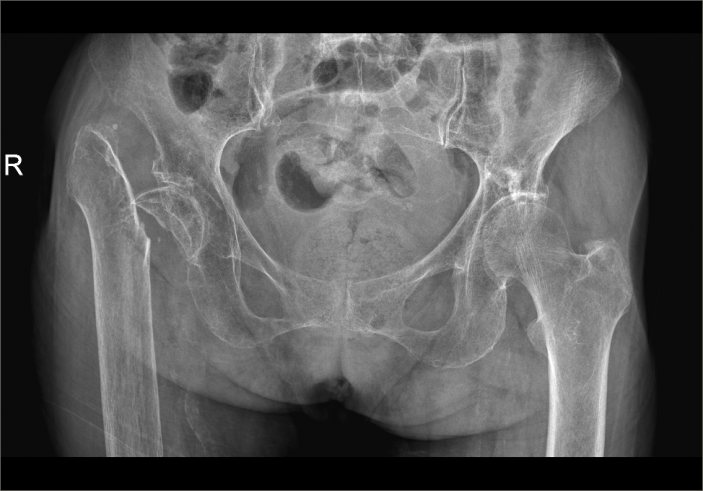

△骨科于15日、16日收治的另外兩位高齡患者

△術前